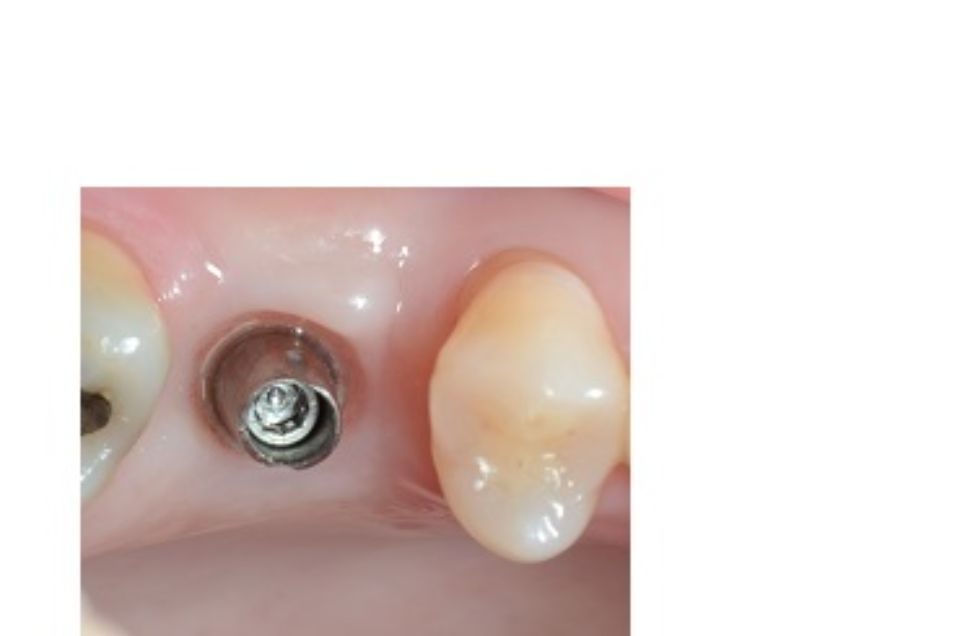

Implantology is the dental specialty that deals with the replacement of the root of the lost tooth.

The replacement is done through a small surgical procedure to place a piece of titanium inside the jawbone.

The implant has a thread inside where the abutment that will support the prosthetic crown will later be screwed on.